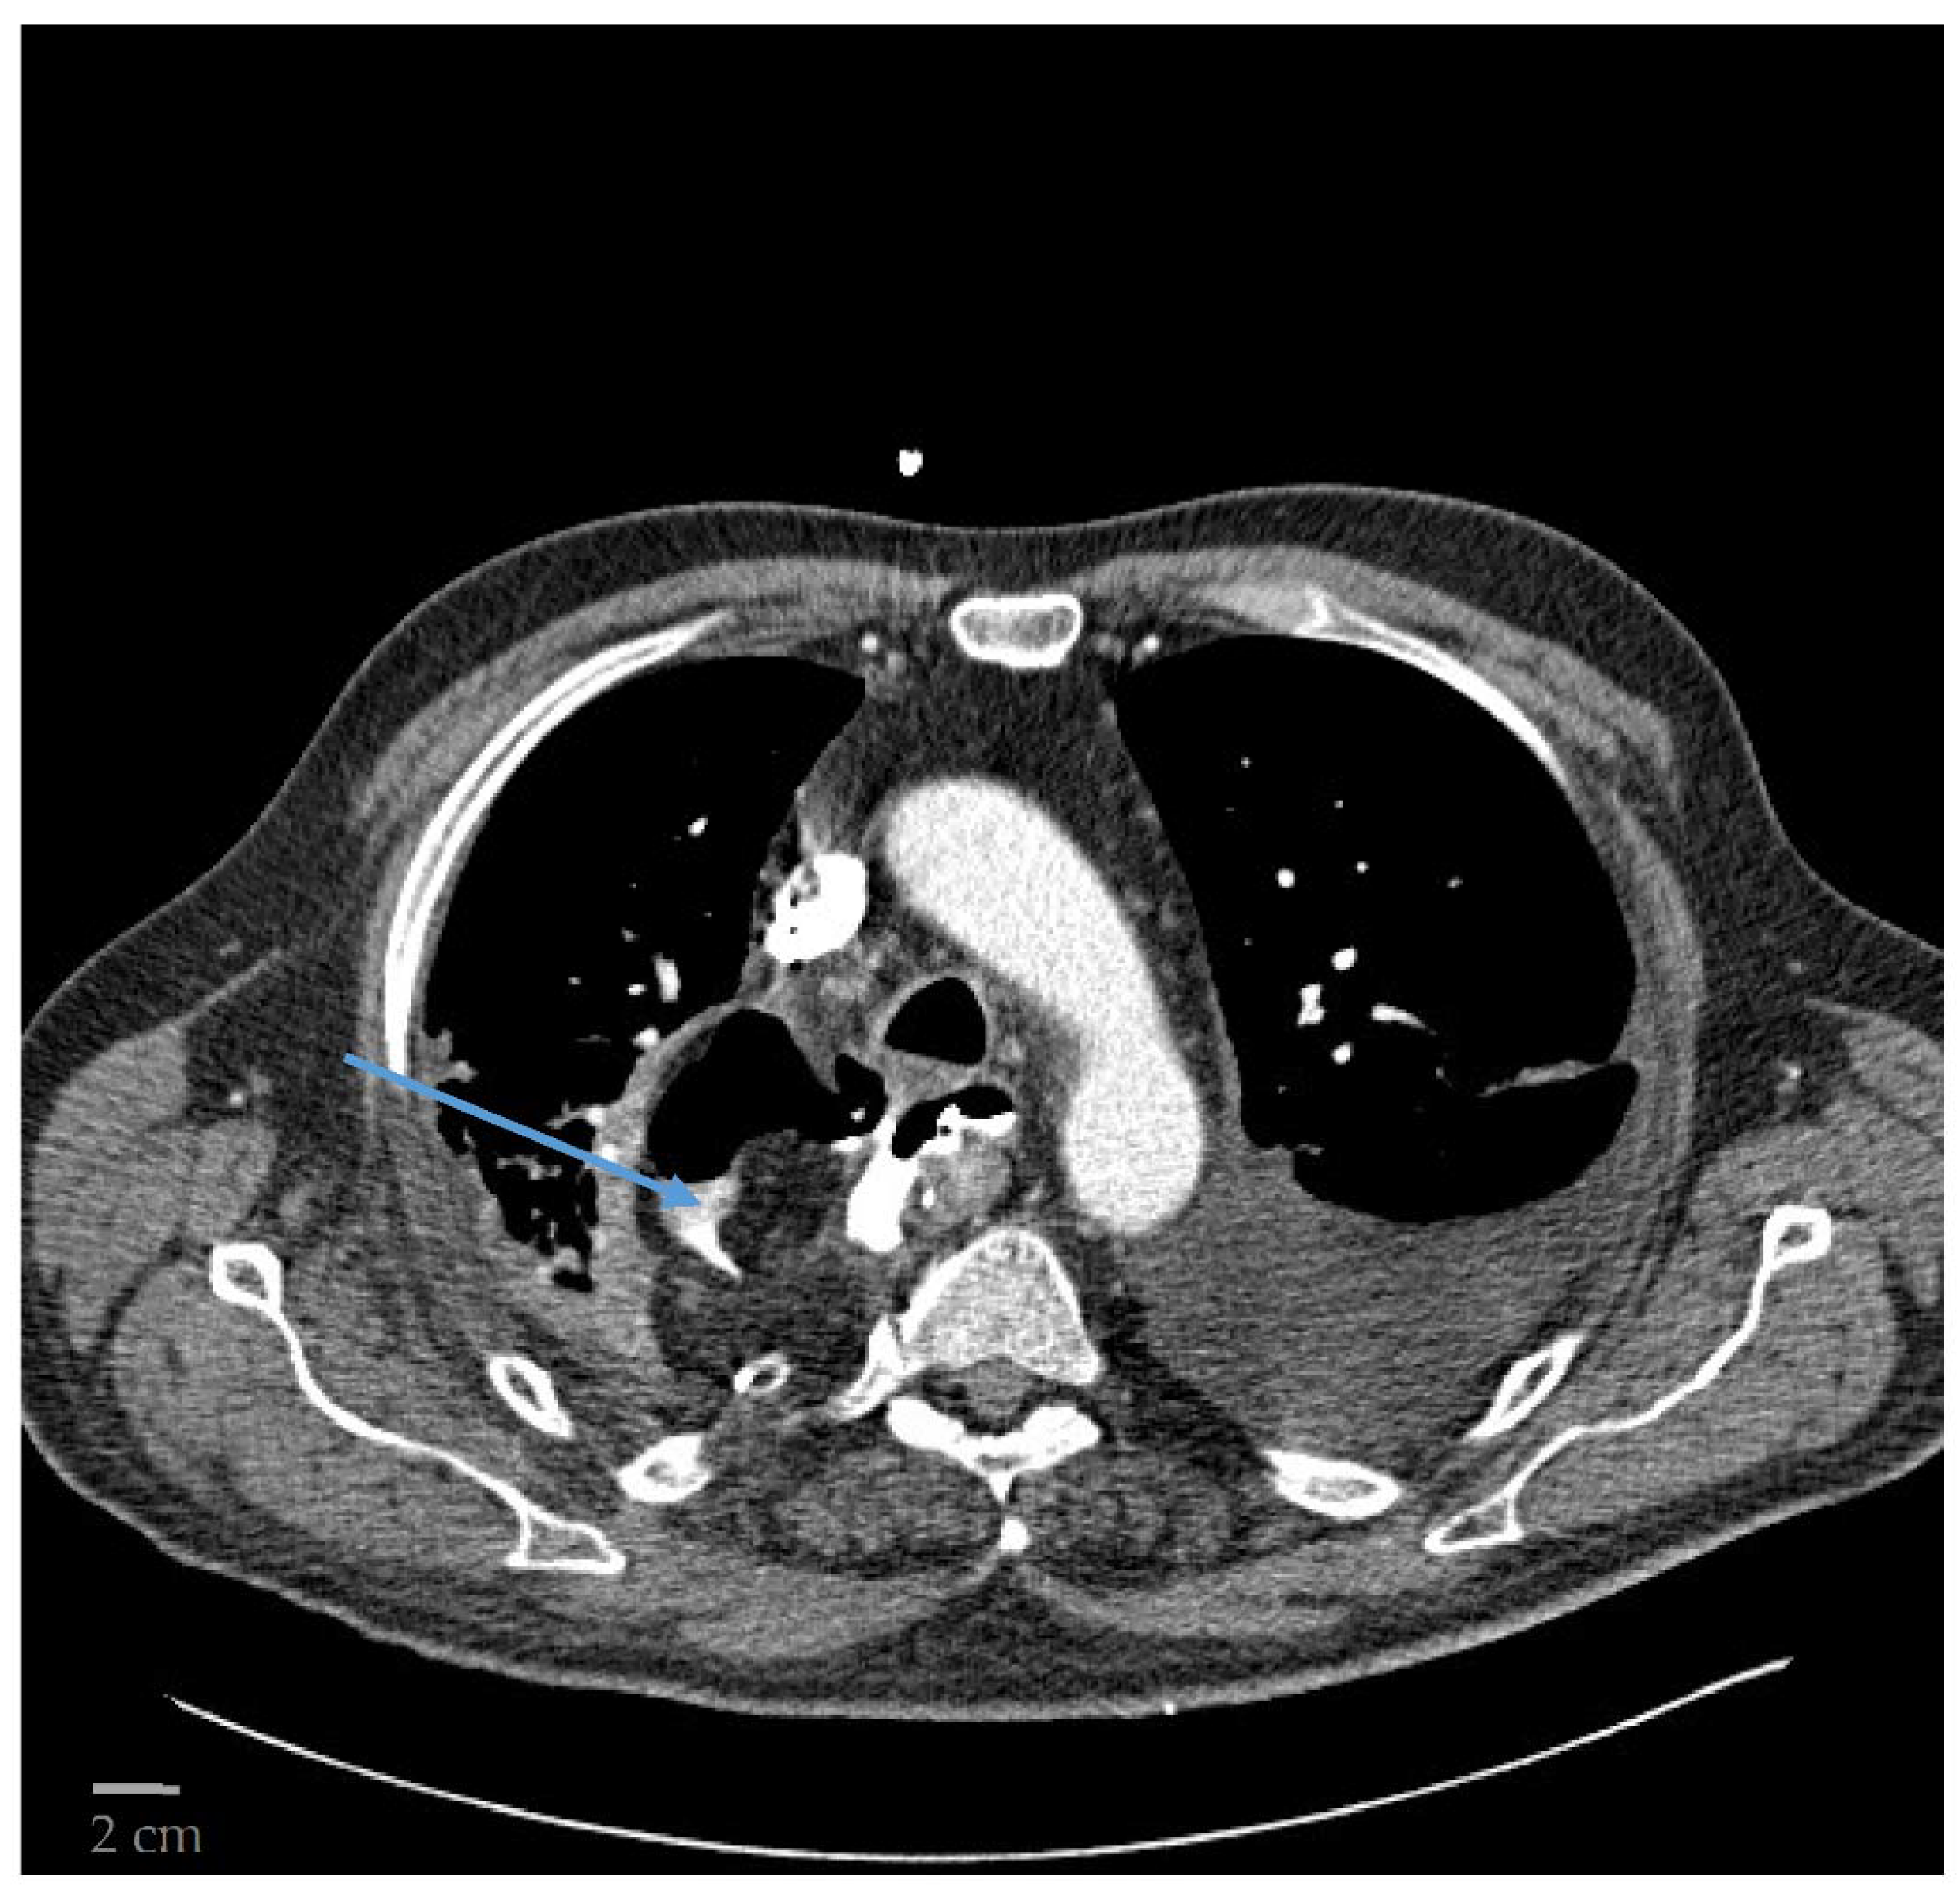

The Canon Aquilion One ® was used in all patients. It has 100 kW of power with a gantry bore of 78 cm and a scan range of 150/200 cm. It rotates at 0.350 s per rotation with a maximum rate of 50 images per second delivered. CT was performed with intravenous and oral contrast agents. Patients were in a supine position and images were acquired while in full inspiration. A 1.5 mL/kg contrast agent was infused intravenously. In addition, 15 mL of contrast agent mixed with 200 mL of water were given orally. Axial images were obtained in slice thicknesses of 3 mm. Extravasation of the contrast agent was defined as an AL. In addition, mediastinal fluid collection and mediastinal air were associated with the presence of an AL (Figure 1). All CT images were reviewed by an experienced radiologist (specialist/consultant).

Figure 1.

CT displaying an AL with extravasation of contrast agent and free air in the mediastinum indicated by the blue arrow.